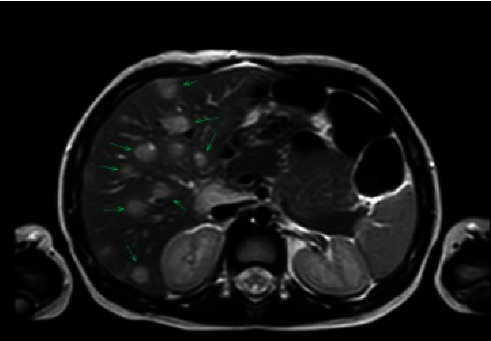

Bartonella henselae is a Gram-negative bacillus transmitted to humans via cat saliva or scratch. Cat scratch disease, the typical clinical manifestation of B. henselae infection, presents as localized cutaneous or regional lymphadenopathy. Rare, atypical presentations, generally reflecting bloodborne disseminated disease, can include hepatosplenic, cardiac, ocular, neurologic, or musculoskeletal involvement. Here, we present a case of disseminated B. henselae with hepatic abscesses and associated ischial osteomyelitis in an immunocompetent 2-year-old male patient. Although osteomyelitis is a rare manifestation of B. henselae infection, it should be included in the differential diagnosis in pediatric patients presenting with fever of unknown origin and musculoskeletal pain, especially in the setting of cat exposure. Hepatic involvement of B. henselae infection is associated with significant morbidity; therefore, abdominal imaging is critical in the diagnostic workup. This patient was successfully treated after a 6-week course of azithromycin and rifampin, as evidenced by symptom resolution and improved fluid collections on repeat imaging. While most cases of B. henselae resolve without treatment, in severe or disseminated infection such as this case, antibiotics such as azithromycin and rifampin should be considered for treatment.

Abstract Image